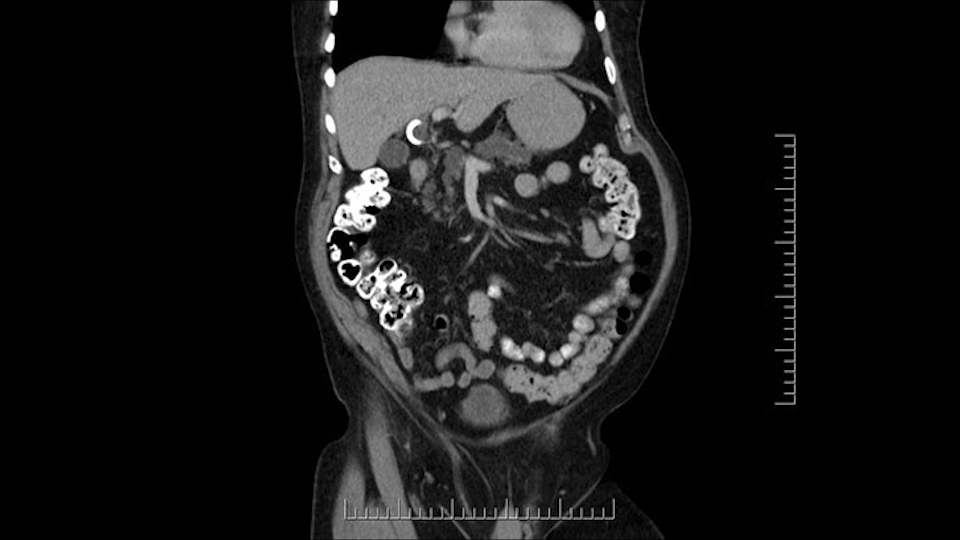

The other thing I look at is the gastroepeiploic arcade- which is this thing here- which is where the gastroepeiploic vein joins the portal vein. I call it the gateway to the neck of the pancreas because you pretty much have to divide it to get to the neck. The middle colic vein usually drains either into it or nearby. I think we’re seeing it here. Again,that can be divided and I usually divide those two and it helps me get under the neck. Again, there’s no issues here with the tumor so it’s nice from that perspective. If I was concerned about the vein, which I’m not here, I would go to the coronal view. It’s a nice way to look at the vein on just a couple of cuts and you can see a beautiful view of it here. There’s the portal vein, there’s the head of the pancreas. There’s the tumor. It’s a little closer here than it looks on the other one. I doubt it’s involved. If it’s touching, it may not be invading it but even if it was, it's a short segment. Anyways, there’s the SMV there’s the splenic vein, and everything looks good. You can see the stent. I ignore the stent. It’s the most dramatic looking thing in the picture but it’s actually the least important.